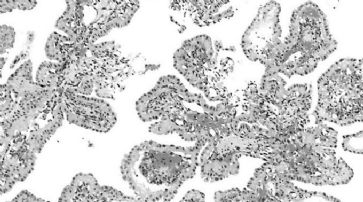

Die Forscher untersuchten die Auswirkungen der Hemmung von Hsp90 bei menschlichen Krebszellen, die mit AR-V7 die häufigste Variante dieser Krebsart produzierten.

Die Krebszellen wurden im Labor gezüchtet und Mäusen injiziert. (Symbolbild) /

Die Krebszellen wurden im Labor gezüchtet und Mäusen injiziert. Es zeigte sich, dass die Hemmung von Hsp90 zu einer Verringerung der Produktion von AR-V7 führte. Dabei handelte es sich um einen neuen und nicht erwarteten Mechanismus. Die Hemmung führte auch zu einer Verringerung des normalen Androgenrezeptors und anderer wichtiger Krebsmoleküle wie AKT und GR.